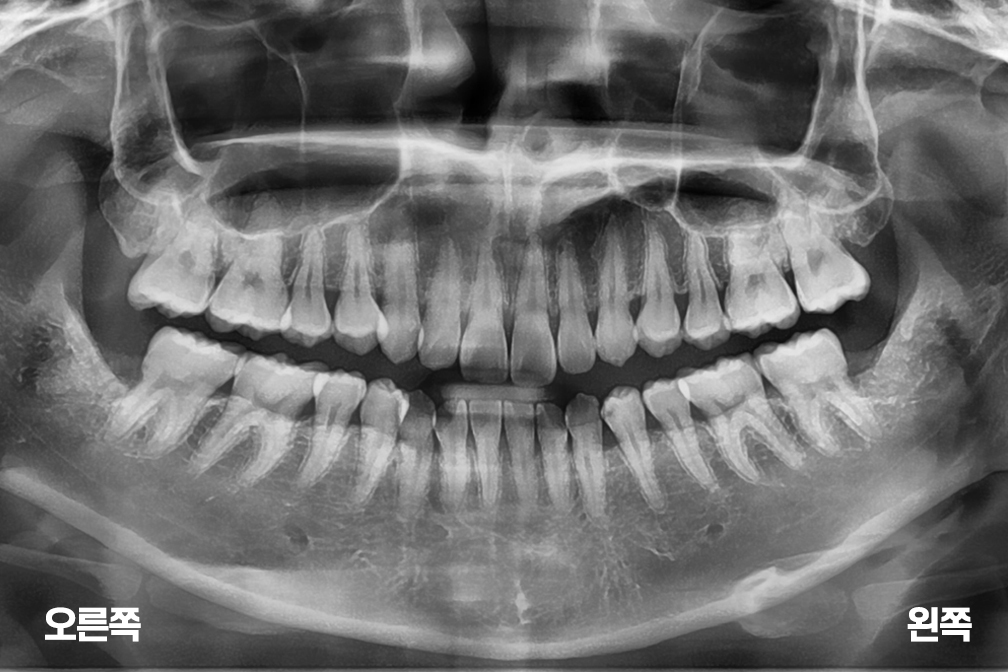

사랑니발치 아래 양쪽 사랑니 발치

사랑니 발치

위 전후사진은 이미지사진으로 실제 눈으로 보는 것과는 다를 수 있으며, 환자의 치아상태과 방법에 따라 치료결과가 다를수 있습니다.

사진의 날짜는 촬영날짜이며 치료의 기간이 아님을 알려드립니다.

치료 후 치아표면의 탈회 , 충치, 치근흡수 등의 부작용이 있을 수 있습니다.